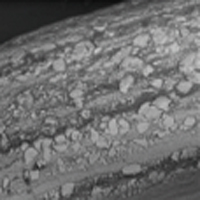

Occluders and vascular plugs are made from pre-oxidised nitinol wires, braided into a highly functional and elastic wire mesh, providing a high level of anatomical conformity. The short top plug design and screw housing are made of pre-oxidised stainless steel. The thickness of the individual wire varies according to size and type to ensure:

Special Heat Treatment of Nitinol Wire

The oxidation process creates a compact and uniform TiO₂ surface on the nitinol wire.

Excellent Haemocompatibility

Titanium oxide films provide the occluder with excellent haemocompatibility after implantation.

Long-Term Safety

The oxide layer effectively prevents the release of nickel ions (50% less than occluders without oxide coating), ensuring improved and earlier endothelialisation.